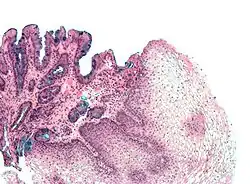

The mucosal layer consists of an epithelial layer, and its underlying supportive tissue, the Lamina Propria. It is separated from the submucosal layer by the Muscularis Mucosa. The epithelial layer varies from section to section of the gut. In the oesophagus it is a non-cornified stratified squamous epithelium; in the stomach it is mainly mucosal cells; the small intestine and large intestine are characterized by absorptive cells, with many mucous producing goblet cells. In the absorptive sections of the intestine, the surface are for absorption is greatly increased by finger-like projections into the lumen called villi, and the absorptive cells themselves also have small projections of microvilli, giving them the appearance of a brush border when viewed with a light microscope.

The surface for absorption is increased in many ways: the mucosa of the small intestine is thrown into folds called rugae; the mucosa itself has numerous finger-like projections called villi, and the epithelial cells are also covered with numerous projections called microvilli. The microvilli give the appearance of a 'brush' on light microscopy; hence the term brush border. The following illustration shows the anatomy of a villi:

Mucous is secreted by numerous goblet cells; other cells are specialized for absorption and are known as absorptive cells. In the base of the crypts are numerous secretory cells which secrete the digestive enzymes of the small intestine. Some of the crypts penetrate into the submucosal layer, forming digestive glands which will communicate with the mucosa via a secretory duct.